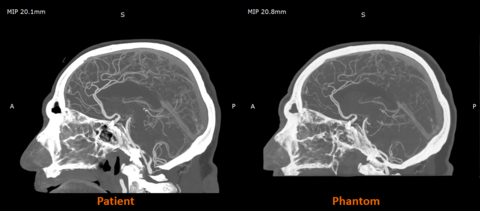

In fact, early work between Stratasys and Siemens Healthineers shows that RadioMatrix can match these values with incredible precision. According to the company, in some tests, deviations were as low as a single HU, which means the scanner can hardly tell the difference between a printed model and actual human tissue. This level of accuracy is rare for any “synthetic phantom” and is what gives RadioMatrix its true impact.

Patient versus Phantom imaging. Image courtesy of Stratasys.